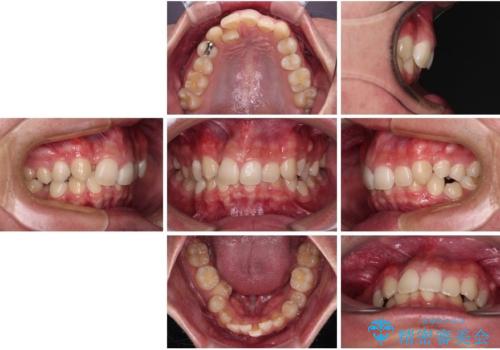

- 今回ご紹介するのは、

「全体的なデコボコ(叢生)」「上下の正中のずれ」 を主訴として来院された20代男性の患者様の症例です。

叢生が強く、歯が並ぶスペースが不足していたため、

上下左右の第一小臼歯を抜歯して、矯正治療のための適切なスペースを確保する計画としました。

上顎左側第一大臼歯に齲蝕が認められたため、矯正治療終了後に 精度の高いセラミックインレー にて修復治療を行いました。